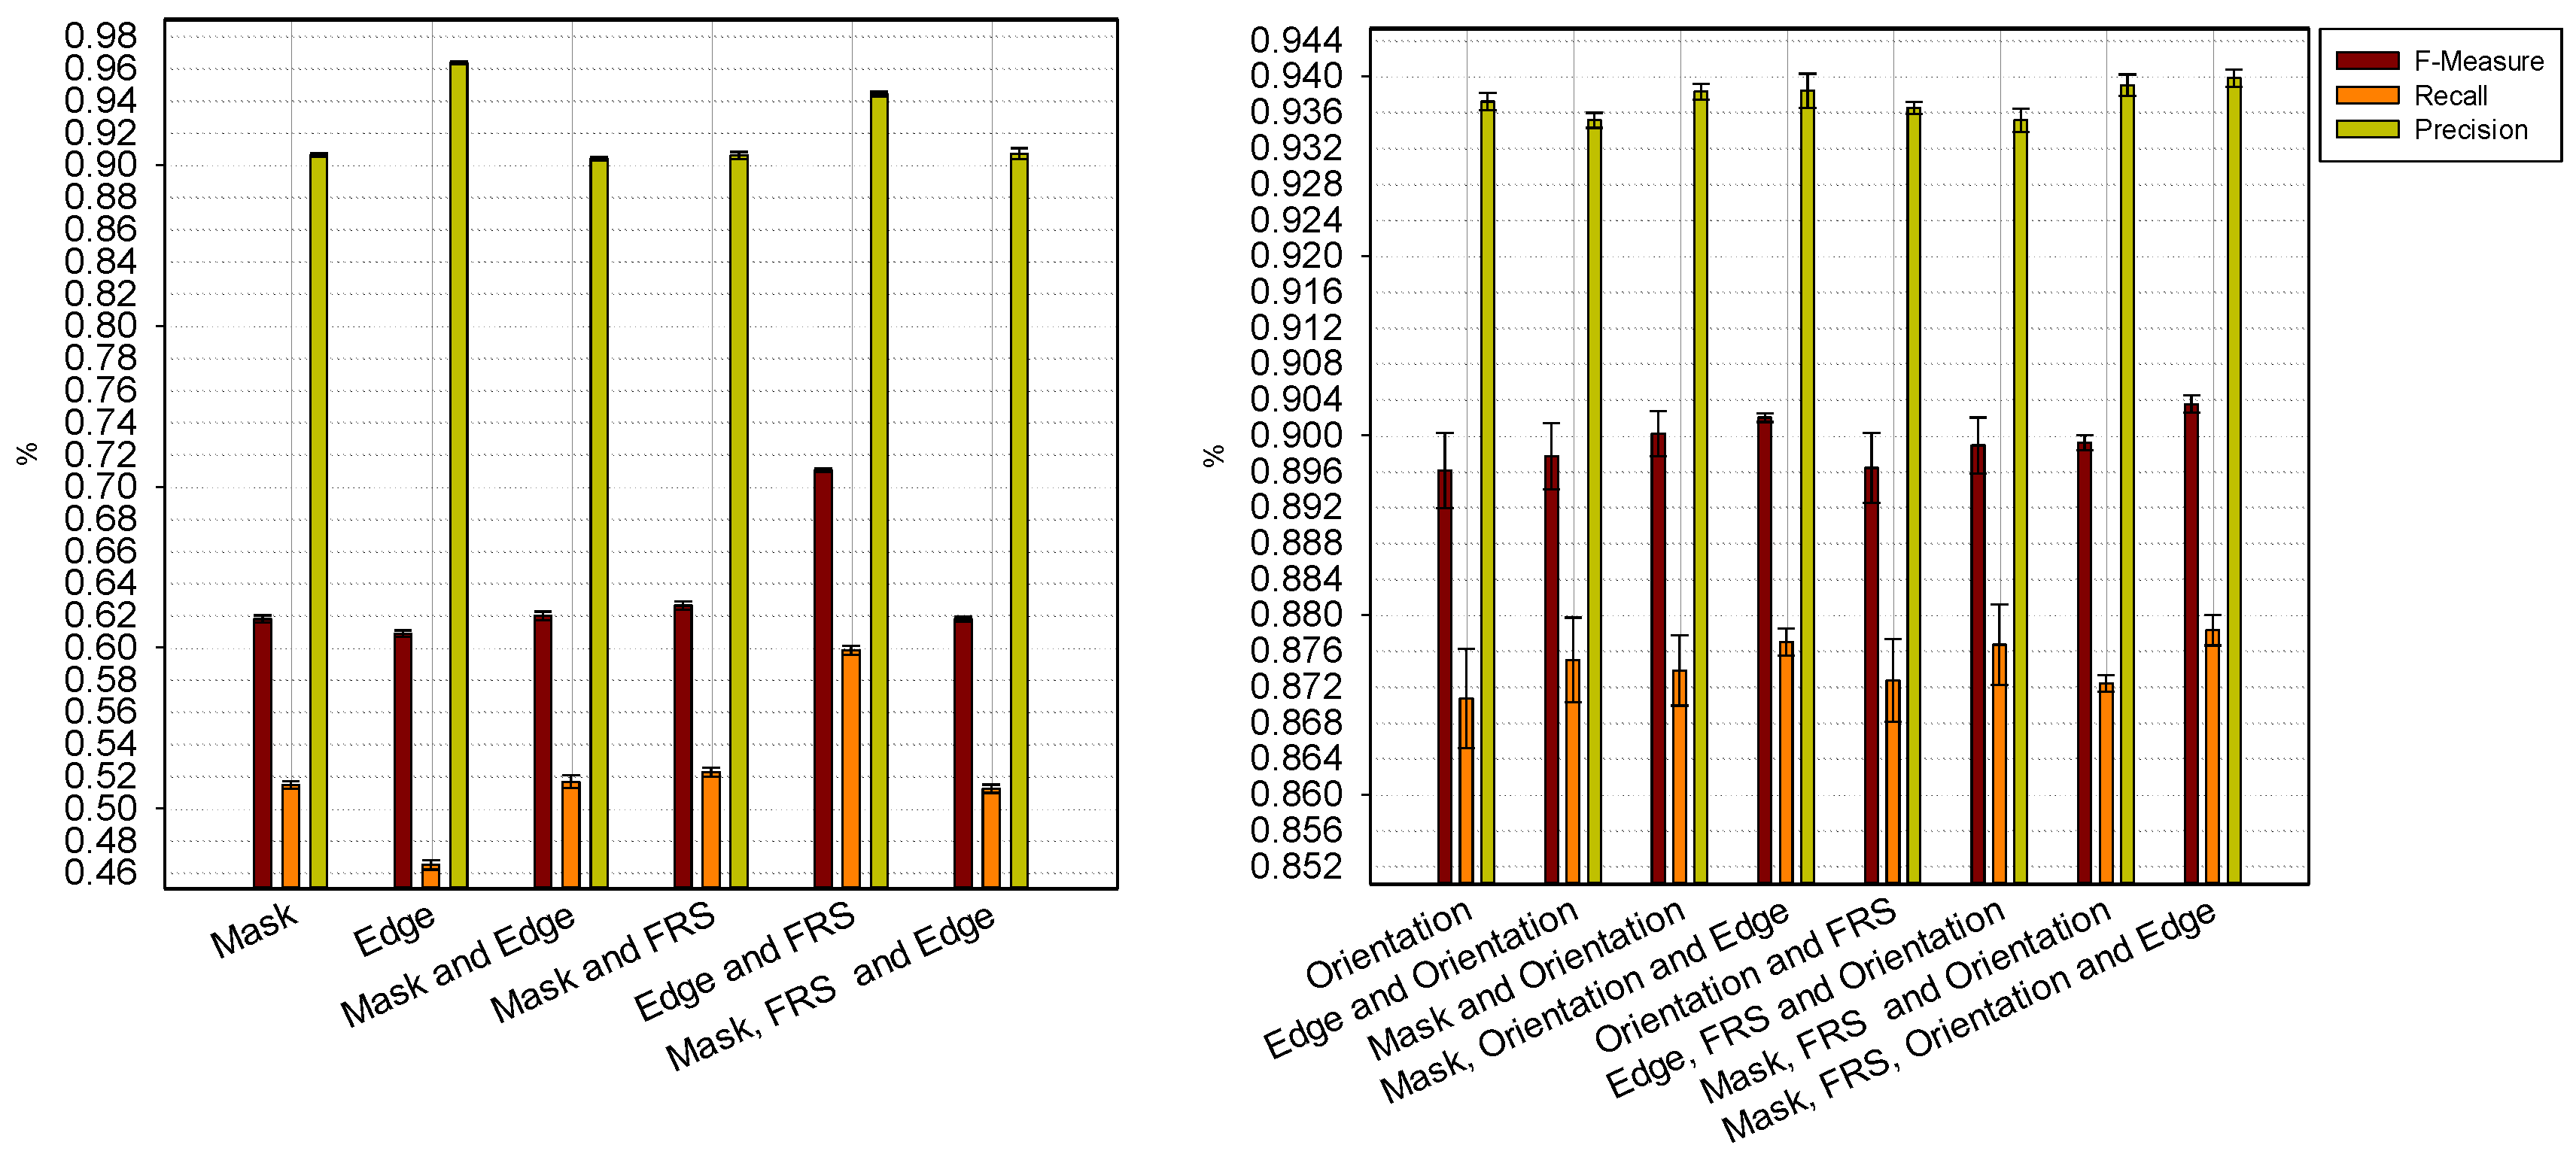

2.2.1. Feature Extraction

, and the magnitude projection image,

, and the magnitude projection image,  .

.

2.2.2. Ellipse Parameter Estimation

), and the pixel orientation, (

), and the pixel orientation, (  ), vector by means of function Av, which defines the angle between both vectors. The second objective function, f𝑔, Equation (22), aims to find shapes with a higher echogenicity given by the LIP-Sobel gra2-dient, Gv. To avoid the gradient generated by small variations in the intensity of the image, a threshold scheme is utilized. The function is set to the gradient if the threshold is higher than a defined value; otherwise, a penalization is applied to avoid the discontinuity in the shape of the ellipse and the gradient map. The third objective function, fb, Equation (23), acts in a similar way as the previous one, but in this case, a binary map, Bv, is used. Finally, the fourth objective function, fFRS, Equation (24), will guide the ellipse into the center of the artery using the FRS map. Once all the objective functions have been defined, the fitness function can be expressed as shown in Equation (25), where the weights, α1,α2,α3,α4, are incorporated for each respective objective function. After empirical tests, it was found that those values fixed to α1 = 100, α2 = 2, α3 = 100, α4 = 30 of the proposed method achieve satisfactory results.

), vector by means of function Av, which defines the angle between both vectors. The second objective function, f𝑔, Equation (22), aims to find shapes with a higher echogenicity given by the LIP-Sobel gra2-dient, Gv. To avoid the gradient generated by small variations in the intensity of the image, a threshold scheme is utilized. The function is set to the gradient if the threshold is higher than a defined value; otherwise, a penalization is applied to avoid the discontinuity in the shape of the ellipse and the gradient map. The third objective function, fb, Equation (23), acts in a similar way as the previous one, but in this case, a binary map, Bv, is used. Finally, the fourth objective function, fFRS, Equation (24), will guide the ellipse into the center of the artery using the FRS map. Once all the objective functions have been defined, the fitness function can be expressed as shown in Equation (25), where the weights, α1,α2,α3,α4, are incorporated for each respective objective function. After empirical tests, it was found that those values fixed to α1 = 100, α2 = 2, α3 = 100, α4 = 30 of the proposed method achieve satisfactory results.